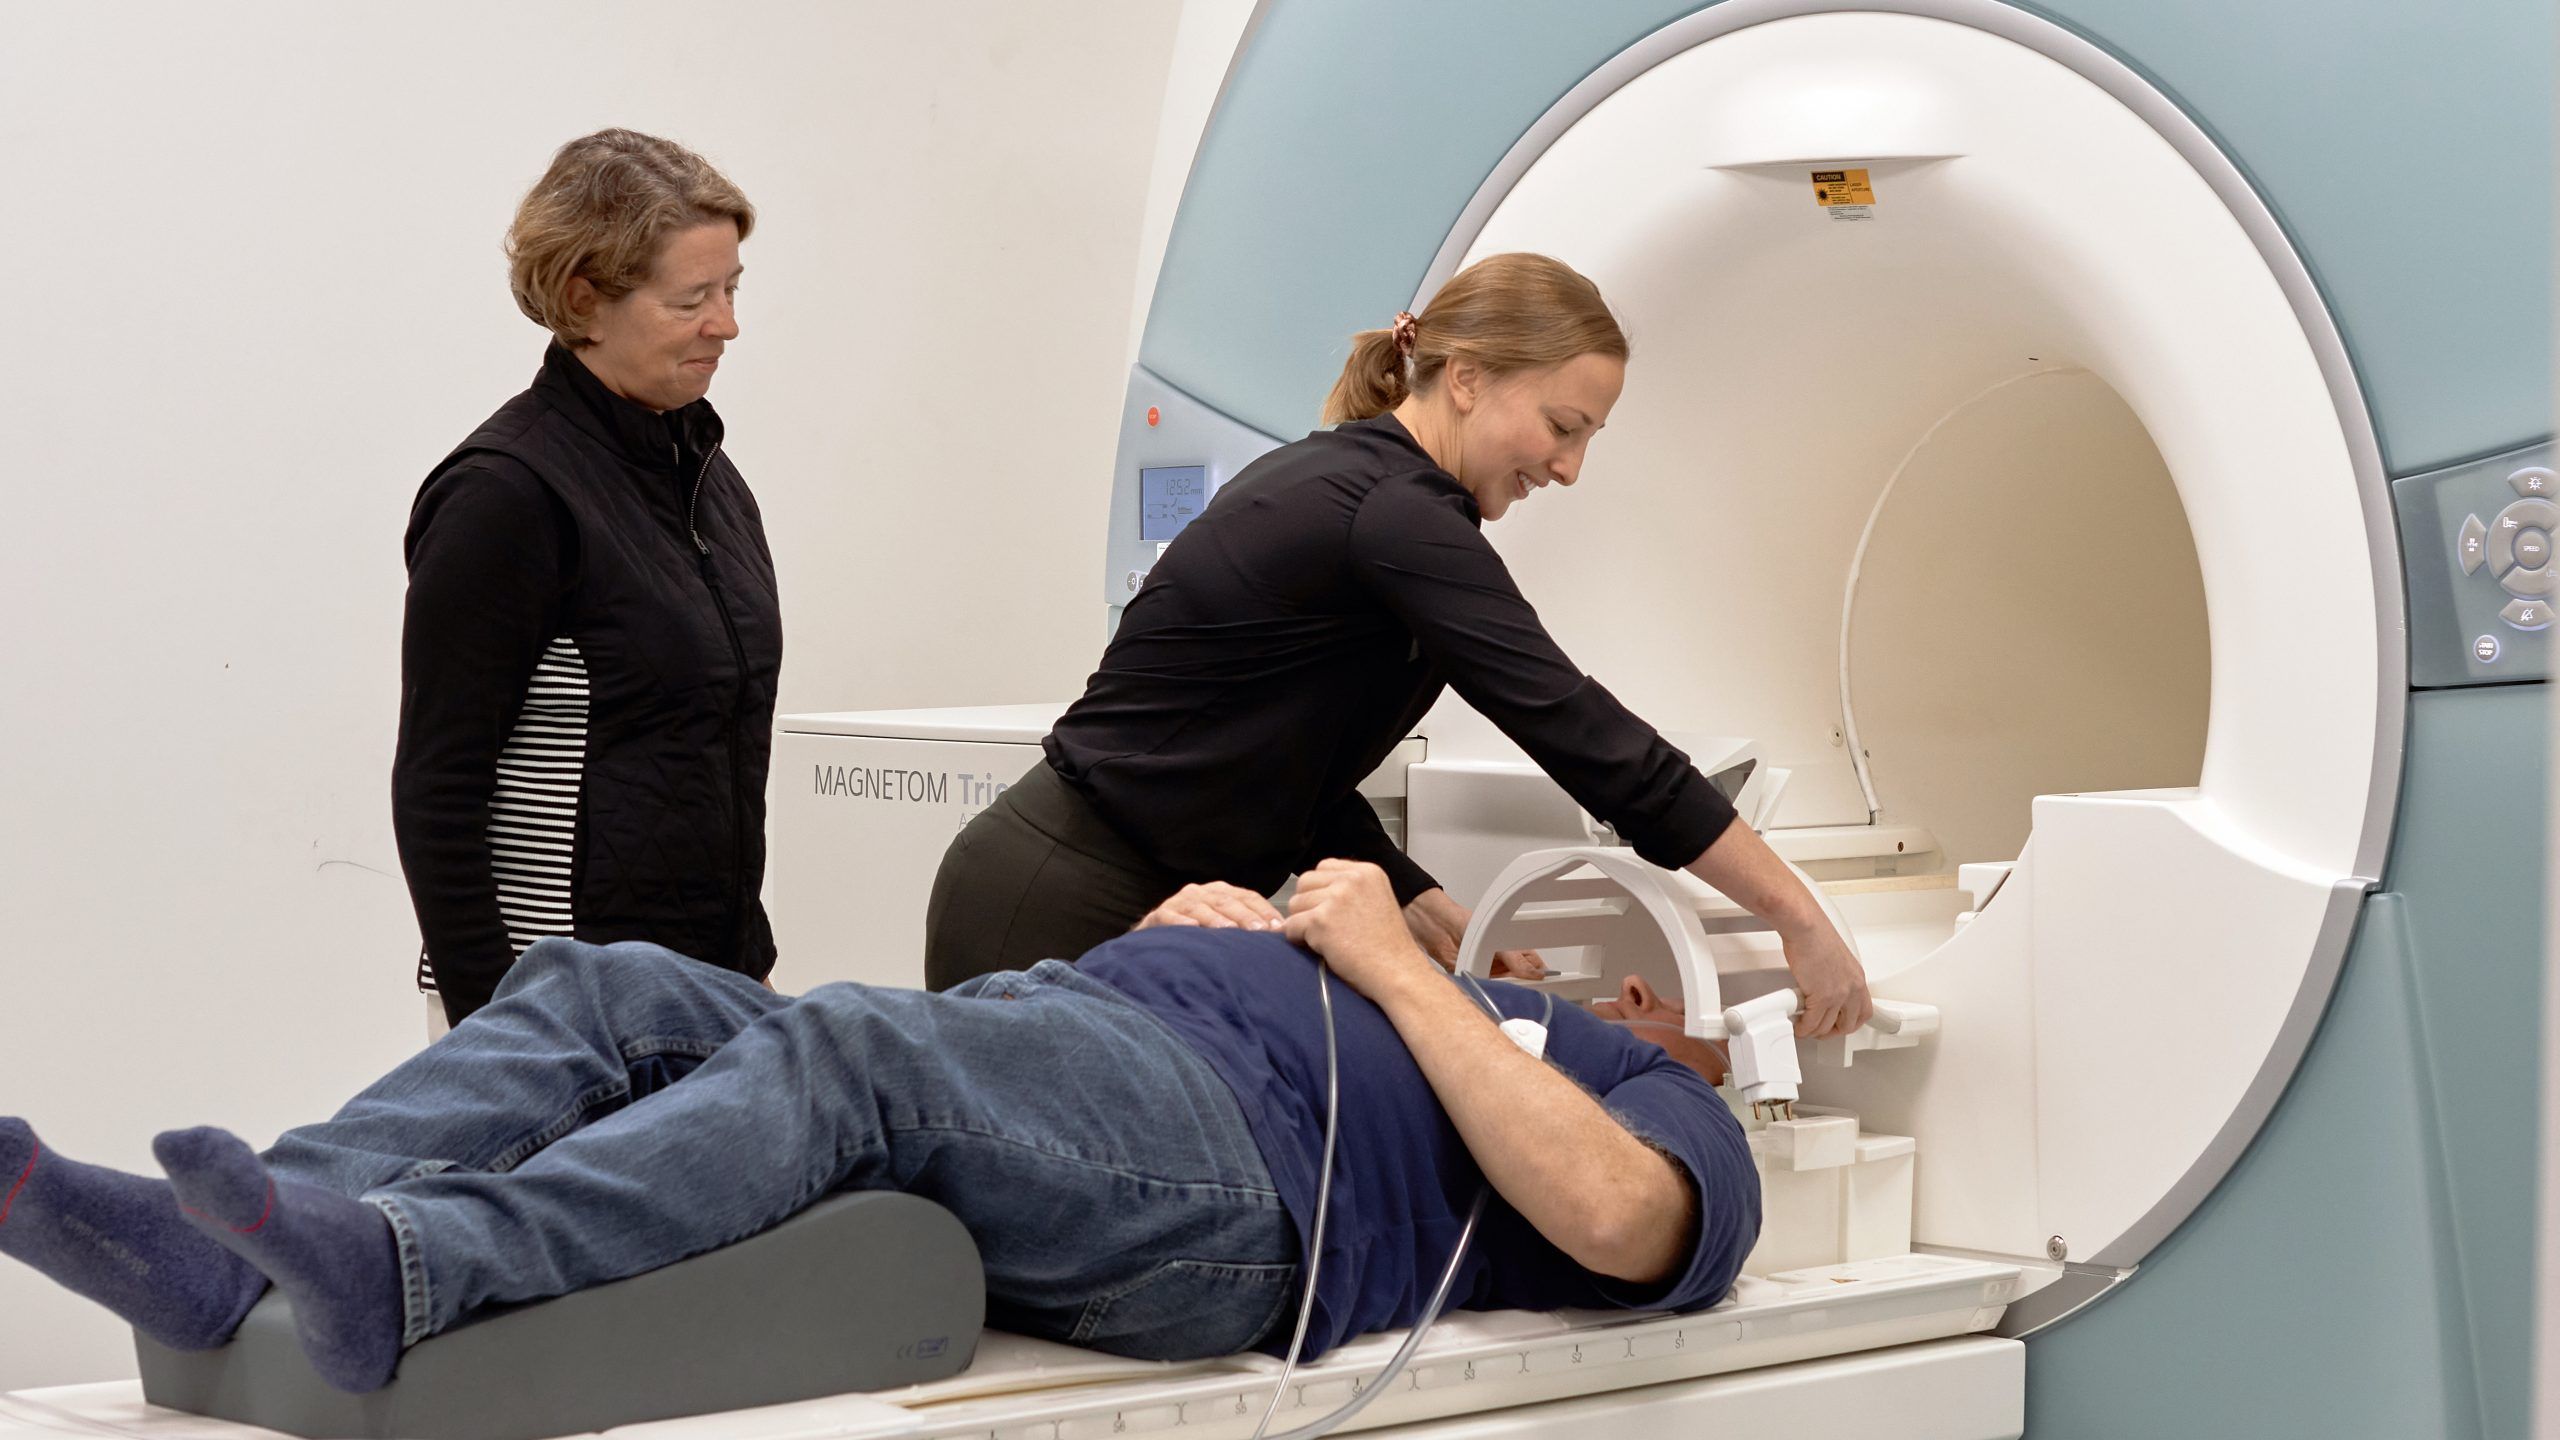

UNCG researchers are using a magnetic resonance imaging machine, or MRI, to peer inside joints and take pictures of study volunteers’ brains. Their goal is to better understand how our bodies and brains function – and why things go wrong – to find ways to prevent common problems.

“It never ceases to amaze me that here at UNCG we have access to this amazing tool to help us ask the questions that we really want to ask,” says Randy Schmitz, professor of kinesiology and director of musculoskeletal imaging at the Gateway UNCG MRI Center, where the MRI is housed.

“This has torn down barriers,” he says. “Our researchers no longer have to go to a medical institution here in town or another academic institution 60 miles away.”